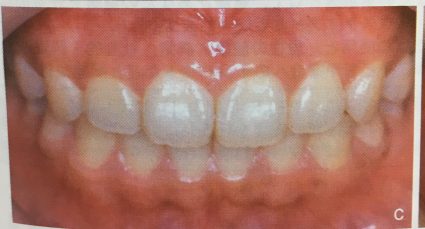

その中で歯ぐきがこのような色を

している方はいらっしゃいませんか?

注目するところは、歯ぐきの色です。

茶色になっているところがありますね。

これは、メラニン色素沈着と言います。

実はこの写真は、10歳のお子さんのお口の中です。

さて、何が原因で歯ぐきがこのような

色になってしまったのでしょうか?

正解はタバコです。